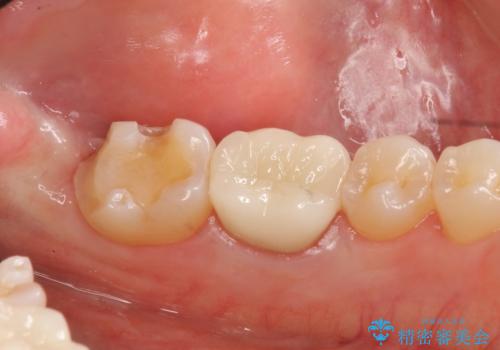

手術後、きちんとマージンラインが歯肉の上に来た状態で、セラミックインレー修復を行いました。

また、左下6番は専門医(銀座院院長 Dr.林)による再根管治療を行いました。

- 38万円(左下7:歯周外科処置5万円、セラミックインレー7万円 左下6:精密根管治療(再治療・専門医による)13万円、ファイバーコア2万円、ジルコニアクラウン10万円、仮歯1万円)費用は治療当時の料金となります